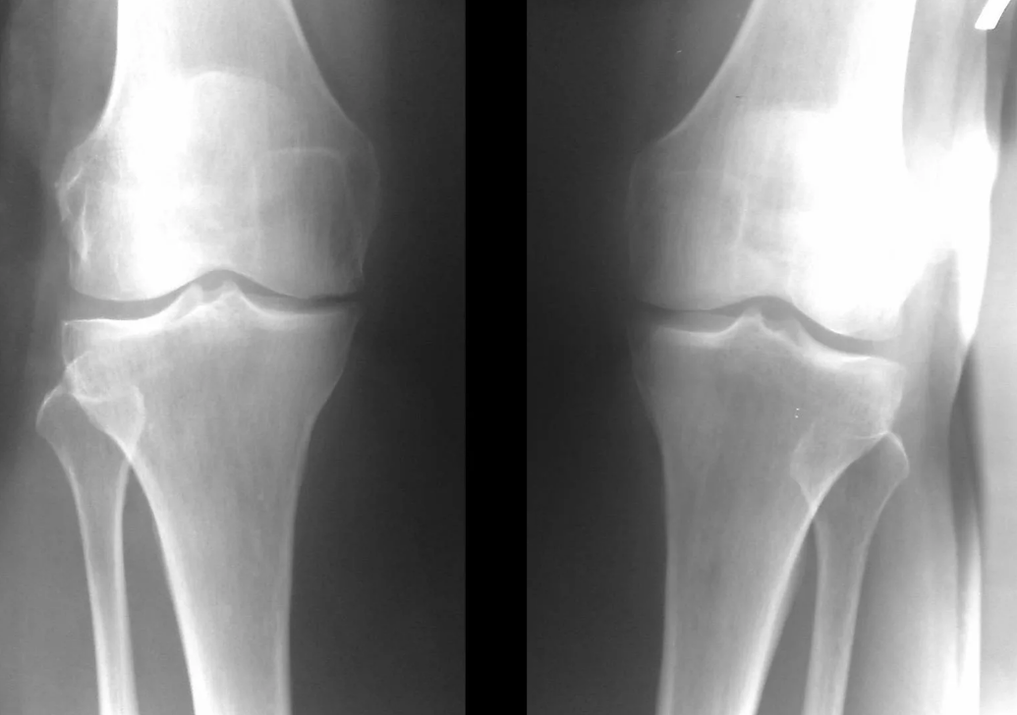

In the vast majority of cases, an examination and an x-ray of the knee joint in two projections (direct and lateral) are sufficient.Clinical data and images help determine the stage of the disease.

In the initial stages of the disease, with minor changes in bone tissue, x-ray examination is not so valuable.At this stage gonarthrosis can be diagnosed by arthroscopy.The precision of the method is very high;only its invasive nature and price can stop it.

In the second phase, the cartilaginous layer becomes significantly thinner and in some places is completely absent.Osteophytes appear along the edges of the joint surfaces.The qualitative and quantitative characteristics of the synovial fluid of the joint change: it becomes denser, more viscous, which leads to a deterioration of its nutritional and lubricating properties.The pain is more prolonged and intense and a crunching sound is often heard during movement.There is mild to moderate limitation of movement and slight deformation of the joint.Taking analgesics helps relieve pain.

Lack of cartilage in most affected areas, severe sclerosis (hardening) of the bone, many osteophytes, and a strong narrowing or absence of the joint space.The pain is almost constant, the gait is impaired.Mobility is severely limited and joint deformation is evident.NSAIDs, physiotherapy and other standard methods for treating knee osteoarthritis are ineffective.